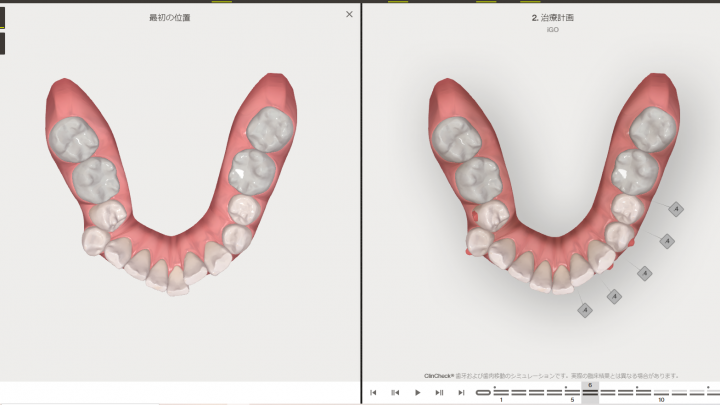

このような左の奥歯(少臼歯)の叢生はインビザラインGoでは不可

下顎左側叢生(がたつき)

このようにiTero5Dplusで再度スキャンすると、どれ位並んだか分かります。

動きが悪いところもわかります。